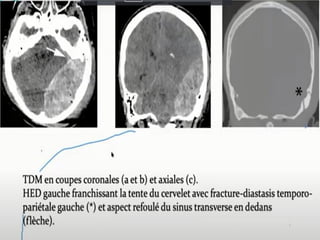

COMPLICATIONS